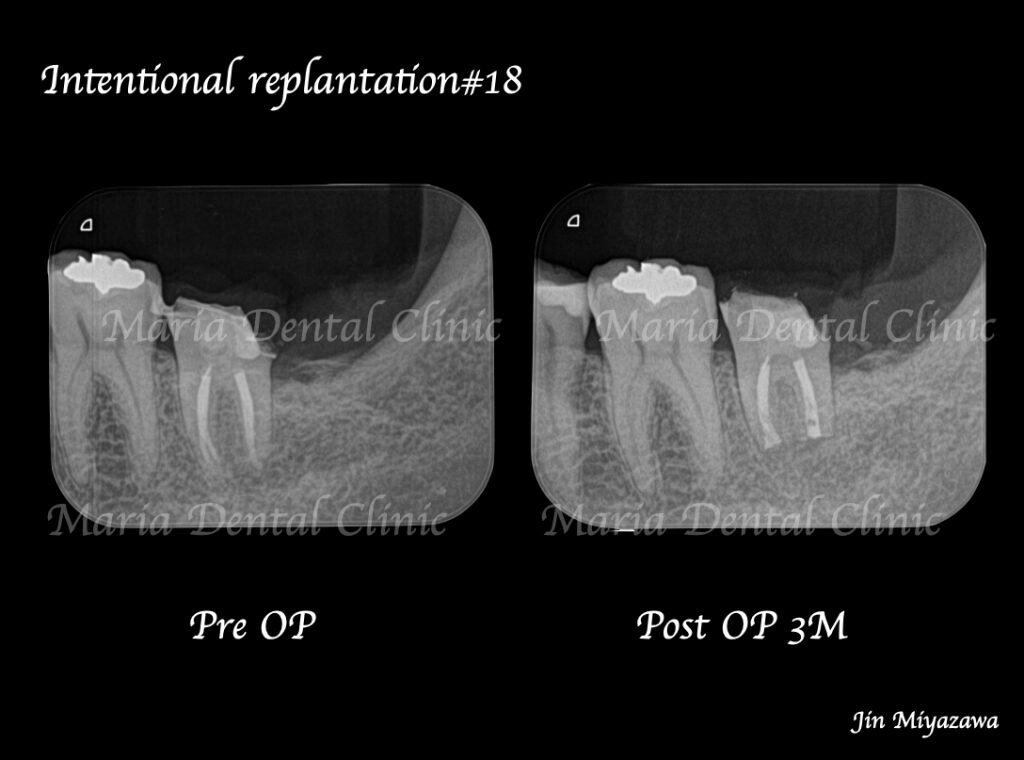

目白マリア歯科【症例】根管治療後も症状の改善が認められないケース・意図的再植・歯根端切除術レントゲン画像術前術後

違和感や痛みは術後1ヶ月程で消失し、3ヶ月後には術直後に見られていた左下7番根尖部に確認できた透過像も消失し、順調に骨が作られていることが確認できます。